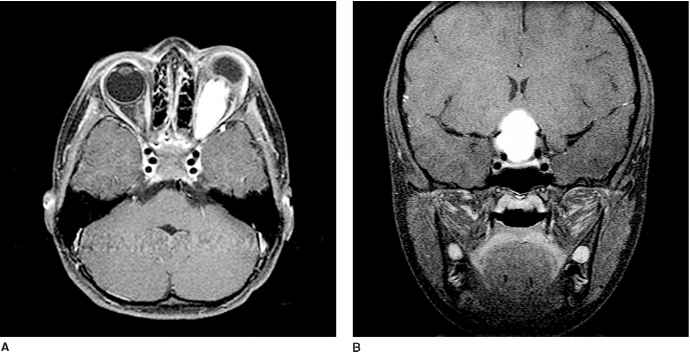

诊断研究包括神经眼科和神经内分泌评估以及脑部MRI。当涉及这种结构时,神经影像学(下图)通常显示视神经的梭形扩大。视神经胶质瘤可在神经外生长并环绕神经。

图示:A,带有造影剂的轴向T1磁共振成像(MRI)证实了一名4岁男孩的左眼视神经胶质瘤,他患有眼球突出和视力丧失。肿瘤还环绕着鞘神经。B,具有对比增强MRI的冠状T1图像显示了嵌合性下丘脑星形细胞瘤。

在视神经鞘内。尽管儿童眼球突出的差异长,但通常可以通过影像学检查证实一条视神经或两条视神经受累。对于下丘脑下丘脑区的病变,典型的球状肿块具有混合的实性和囊性病变,对比度增强。涉及下颌下丘脑区域的病变具有更大的差异。如果有NF1病史,则可以确诊为下视神经下丘脑神经胶质瘤,但是如果没有NF1病史,则通常需要进行活检以明确诊断。通常通过影像学清晰地确定诸如颅咽神经瘤的病变,而下视神经下丘脑神经胶质瘤很少钙化,但是除非是影像学检查表明肿瘤浸润了视神经或视线辐射,否则在非NF1病患中,诸如生殖细胞肿瘤之类的实体肿块可能会被误认为是嵌合性下丘脑神经胶质瘤。